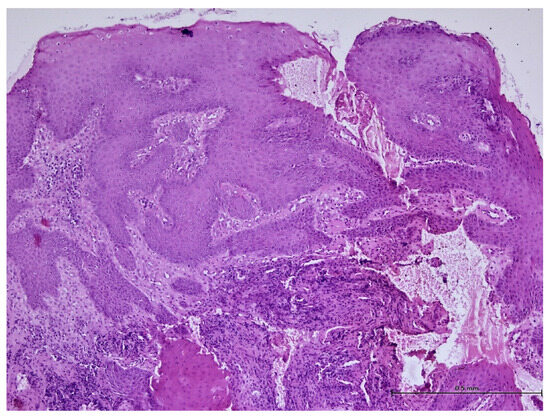

A Retrospective Histological Study on Palatal and Gingival Mucosa Changes during a Rapid Palatal Expansion Procedure

3. Results